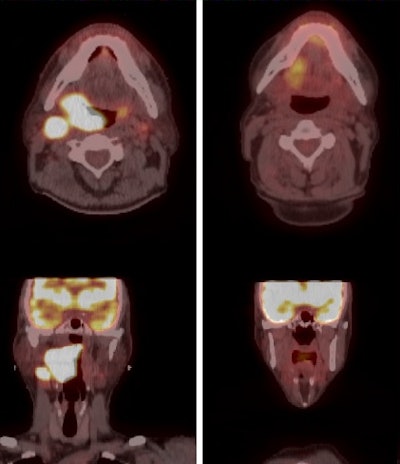

A three-month follow-up PET/CT scan is very helpful for detecting the recurrence of oropharyngeal cancer and predicting the overall survival of patients treated with radiation therapy, according to a study presented at the recent American Society for Radiation Oncology (ASTRO) Multidisciplinary Head and Neck Cancer Symposium in Scottsdale, AZ.

Researchers from H. Lee Moffitt Cancer Center in Tampa, FL, found that the combination of imaging and a physical exam three months after radiation treatment identified 92% of cancer recurrences at the original site of the tumor. It also detected tumor spread, as well as 71% of distant cancer growth. The early three-month evaluation also contributed to a three-year overall patient survival rate of 91%.

The three-year regional control rate was 95%. Among nine patients with regional recurrences, eight (89%) were discovered through the three-month post-treatment PET/CT or from symptoms. Patients with five nodes or level 4 lymph nodes were more likely to have regional failure (p < 0.05).

The three-year locoregional control rate was 94%. Of the 13 individuals who developed locoregional cancer, 12 (92%) presented with symptoms or persistent disease on follow-up PET/CT. The three-year rate of freedom from distant metastases was 91%, with an increased risk of metastases in patients with a lymph node larger than 6 cm, bilateral lymphadenopathy, five or more nodes, or a lymph node present in level 4 (p < 0.05).

Of the 21 patients who had distant cancer recurrence, symptoms or three-month post-treatment imaging were credited with finding 15 (71%) of those cases.

The researchers concluded that if a three-month, post-treatment PET/CT scan is negative, no additional imaging is needed unless other symptoms arise.